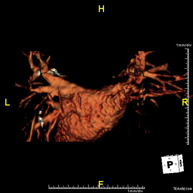

- Thoracic aorta MRI angiography

This non-invasive diagnostic procedure uses an electromagnetic field and radio waves (from a transmitter and receiver) to acquire high-definition anatomical images of the thoracic aorta. It is a radiation-free procedure. In most cases, paramagnetic contrast (gadolinium) is required. It enables non-invasive angiographic studies using a gadolinium injection, with subsequent 2D and 3D reconstruction using specialised workstations. It also includes an aortic valve examination, which is essential information if the patient needs surgery. This test is especially indicated in patients requiring surgical processing (such as pre-surgical vascular mapping), in the tracking of patients with aortic aneurysms, etc.